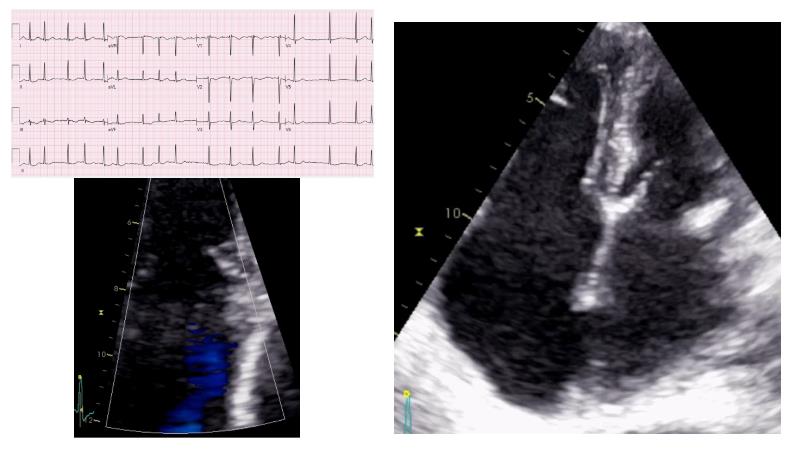

Based on an in-depth review of the data from TRILUMINATE pivotal, a randomized trial whose findings were recently published in the NEW ENGLAND JOURNAL of MEDICINE, this lecture explains how these results will impact clinical practice in the treatment of tricuspid regurgitation. Join the speakers and learn more.

- To understand why it is key to intervene in tricuspid regurgitation disease - A safe option for an unmet need

- To learn how TRILUMINATE Pivotal - the first randomised trial - is impacting the clinical practice in tricuspid regurgitation treatment